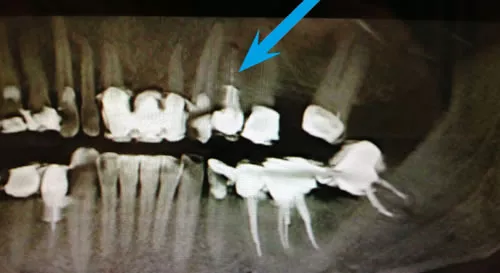

Warum reicht ein 2D-Röntgen manchmal nicht aus?

Oft klagen Patient:innen über Zahnschmerzen, doch auf einem herkömmlichen zweidimensionalen Röntgenbild (Einzelbild oder Panoramaaufnahme) ist keine eindeutige Ursache erkennbar. Das liegt nicht an einem Diagnosefehler des Zahnarztes – sondern daran, dass räumliche Tiefe (die 3. Dimension) auf solchen Bildern nicht darstellbar ist.

Beispiel:

Ein Zahn scheint auf dem 2D-Bild unauffällig. Doch das 3D-Röntgen (DVT) zeigt, dass eine der Wurzeln sich in einem knochenfreien Bereich befindet – ein eindeutiger Hinweis auf Entzündung oder Knochenabbau.

Zweidimensionales Röntgenbild der Zähne – Limitierungen der 2D-Röntgendiagnostik erklärt in der ACC Zahnklinik Basel

3D-Röntgen (DVT) für präzise Zahn- und Kieferdiagnostik – moderne Bildgebung in der ACC Zahnklinik Basel

3D-Röntgendiagnostik mit DVT – exakte Einblicke in den Kiefer

Das digitale Volumentomogramm (DVT) ermöglicht eine dreidimensionale Darstellung des Kiefers. Damit erkennt man:

• Welche Wurzel betroffen ist (buccal oder palatinal)

• Das genaue Ausmass von Knochenabbau

• Entzündungsherde, die im 2D-Bild unsichtbar bleiben

• Anatomische Strukturen für präzise Implantatplanung

DVT statt CT:

Früher war das CT (Computertomographie) die einzige Möglichkeit für 3D-Diagnostik, aber mit hoher Strahlendosis und hohen Kosten. Heute bietet das DVT eine deutlich geringere Strahlenbelastung – vergleichbar mit einem digitalen Panoramaröntgen – bei präziser 3D-Bildgebung.